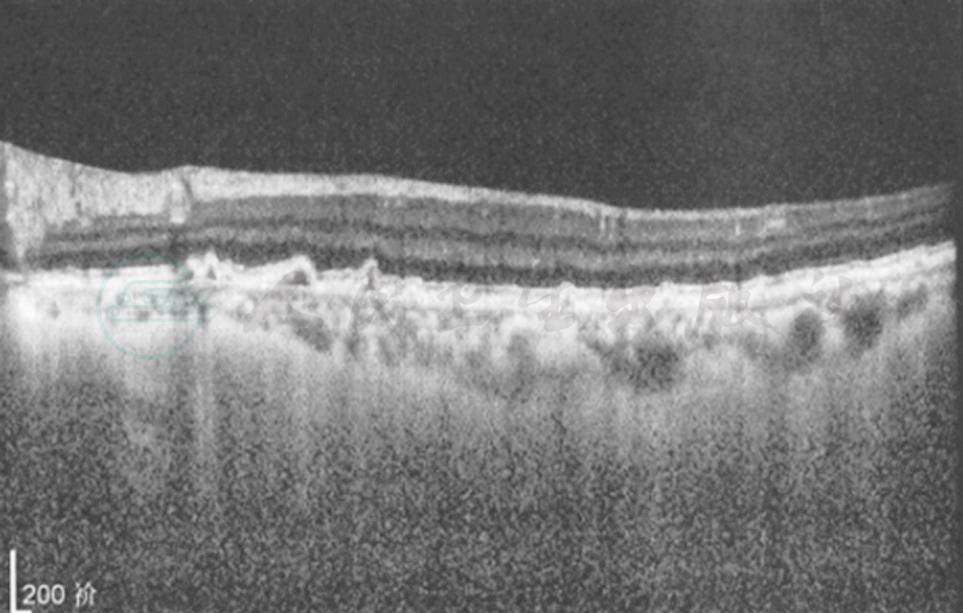

本病为非霍奇金B细胞大淋巴瘤,主要侵犯中枢神经系统与眼的玻璃体及视网膜。近年来发病明显增加,可能与AID病的发病率增加有关,但在我国还与我们对本病认识的提高相关。据复旦大学附属眼耳鼻喉科医院病例,发病年龄在41~84岁间,平均(55.69±12.55)岁。男女无明显差异,可能女性稍高。80%双眼受累。眼部症状往往先于神经系统症状,眼淋巴瘤患者最后85%发生中枢神经系统淋巴瘤,并是导致患者死亡的主要原因。先有中枢神经系统淋巴瘤的患者中,15%~25%以后将发生眼内淋巴瘤,也有两处同时发生的。原发性眼内淋巴瘤的主要症状为无痛性视力下降及飞蚊症。检查以表现单纯玻璃体炎者最多,达50%以上。玻璃体内可见簇状、片状或云雾样灰白色细胞浸润,周边部浓密,向中央渐稀疏,视网膜可无病变。其次为视网膜深层色素上皮下有黄白色、扁平的肿瘤浸润病灶,大小不一,可融合成片,视网膜病变可伴有或不伴玻璃体混浊。上述两种为眼内淋巴瘤的典型表现,非典型表现则多种多样。有沿血管旁浸润,有如树枝挂霜样血管炎;肿瘤侵犯视网膜表现为黄白色的视网膜坏死灶,如同急性视网膜坏死综合征表现;由于色素上皮遭破坏可出现渗出性视网膜脱离;少数情况下也有表现为孤立的眼内肿瘤;瘤细胞如侵犯视盘,则有类似视神经炎或视盘水肿的表现。极少数的情况下肿瘤可自行消退,原病灶处出现斑点状的色素上皮增生或去色素改变。眼前节可有角膜后KP、虹膜结节、房水细胞及闪辉征阳性,这些体征缺乏特异性,但虹膜无后粘连往往提示非葡萄膜炎症。辅助检查方面:B超显示局部球壁隆起或弥漫性球壁增厚,内反射呈低回声。荧光血管造影早期浸润病变呈低荧光,后期呈高荧光,可能伴有血管炎改变。OCT在色素上皮与Bruch膜间有高反射物质为其特征改变(图1)。

图1 OCT示视网膜下肿瘤浸润